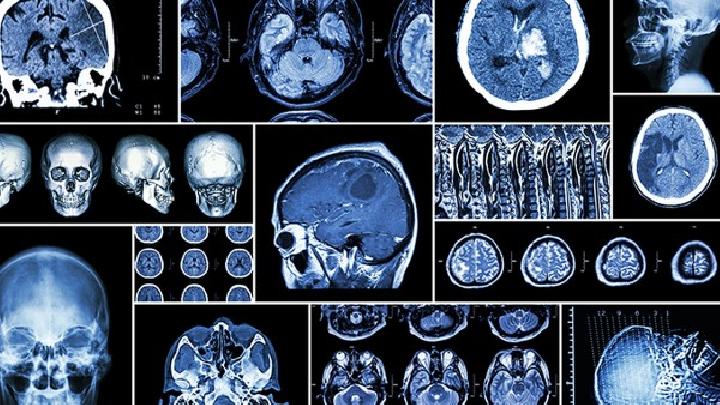

1.CT首选临床疑诊脑出血检查CT检查可显示圆形或卵圆形均匀高密度血肿,边界清晰,血肿部位、大小、形状确定,是否破裂脑室,血肿周围水肿带和占位效应;如大量血液可见高密度铸造,脑室扩张。l周后血肿周围环形增强,吸收后血肿变成低密度或囊性变化。CT进展性脑出血可通过动态观察发现。

2.MRI可发现检查 CT不确定的脑干或小脑出血可在4~5周后区分病程CT无法识别的脑出血,区别于脑出血和脑梗死,显示血管畸形。出血时间可根据血肿信号的动态变化(受血肿内血红蛋白变化的影响)来判断。①超急性期(0~2h):血肿为T1低信号、T2与脑梗死不易区分高信号;②急性期(2~48h):为T1等信号、T2低信号;③亚急性期(3天~3周):T1、T2均为高信号;④慢性期(>3周):呈Tl低信号、T2高信号。